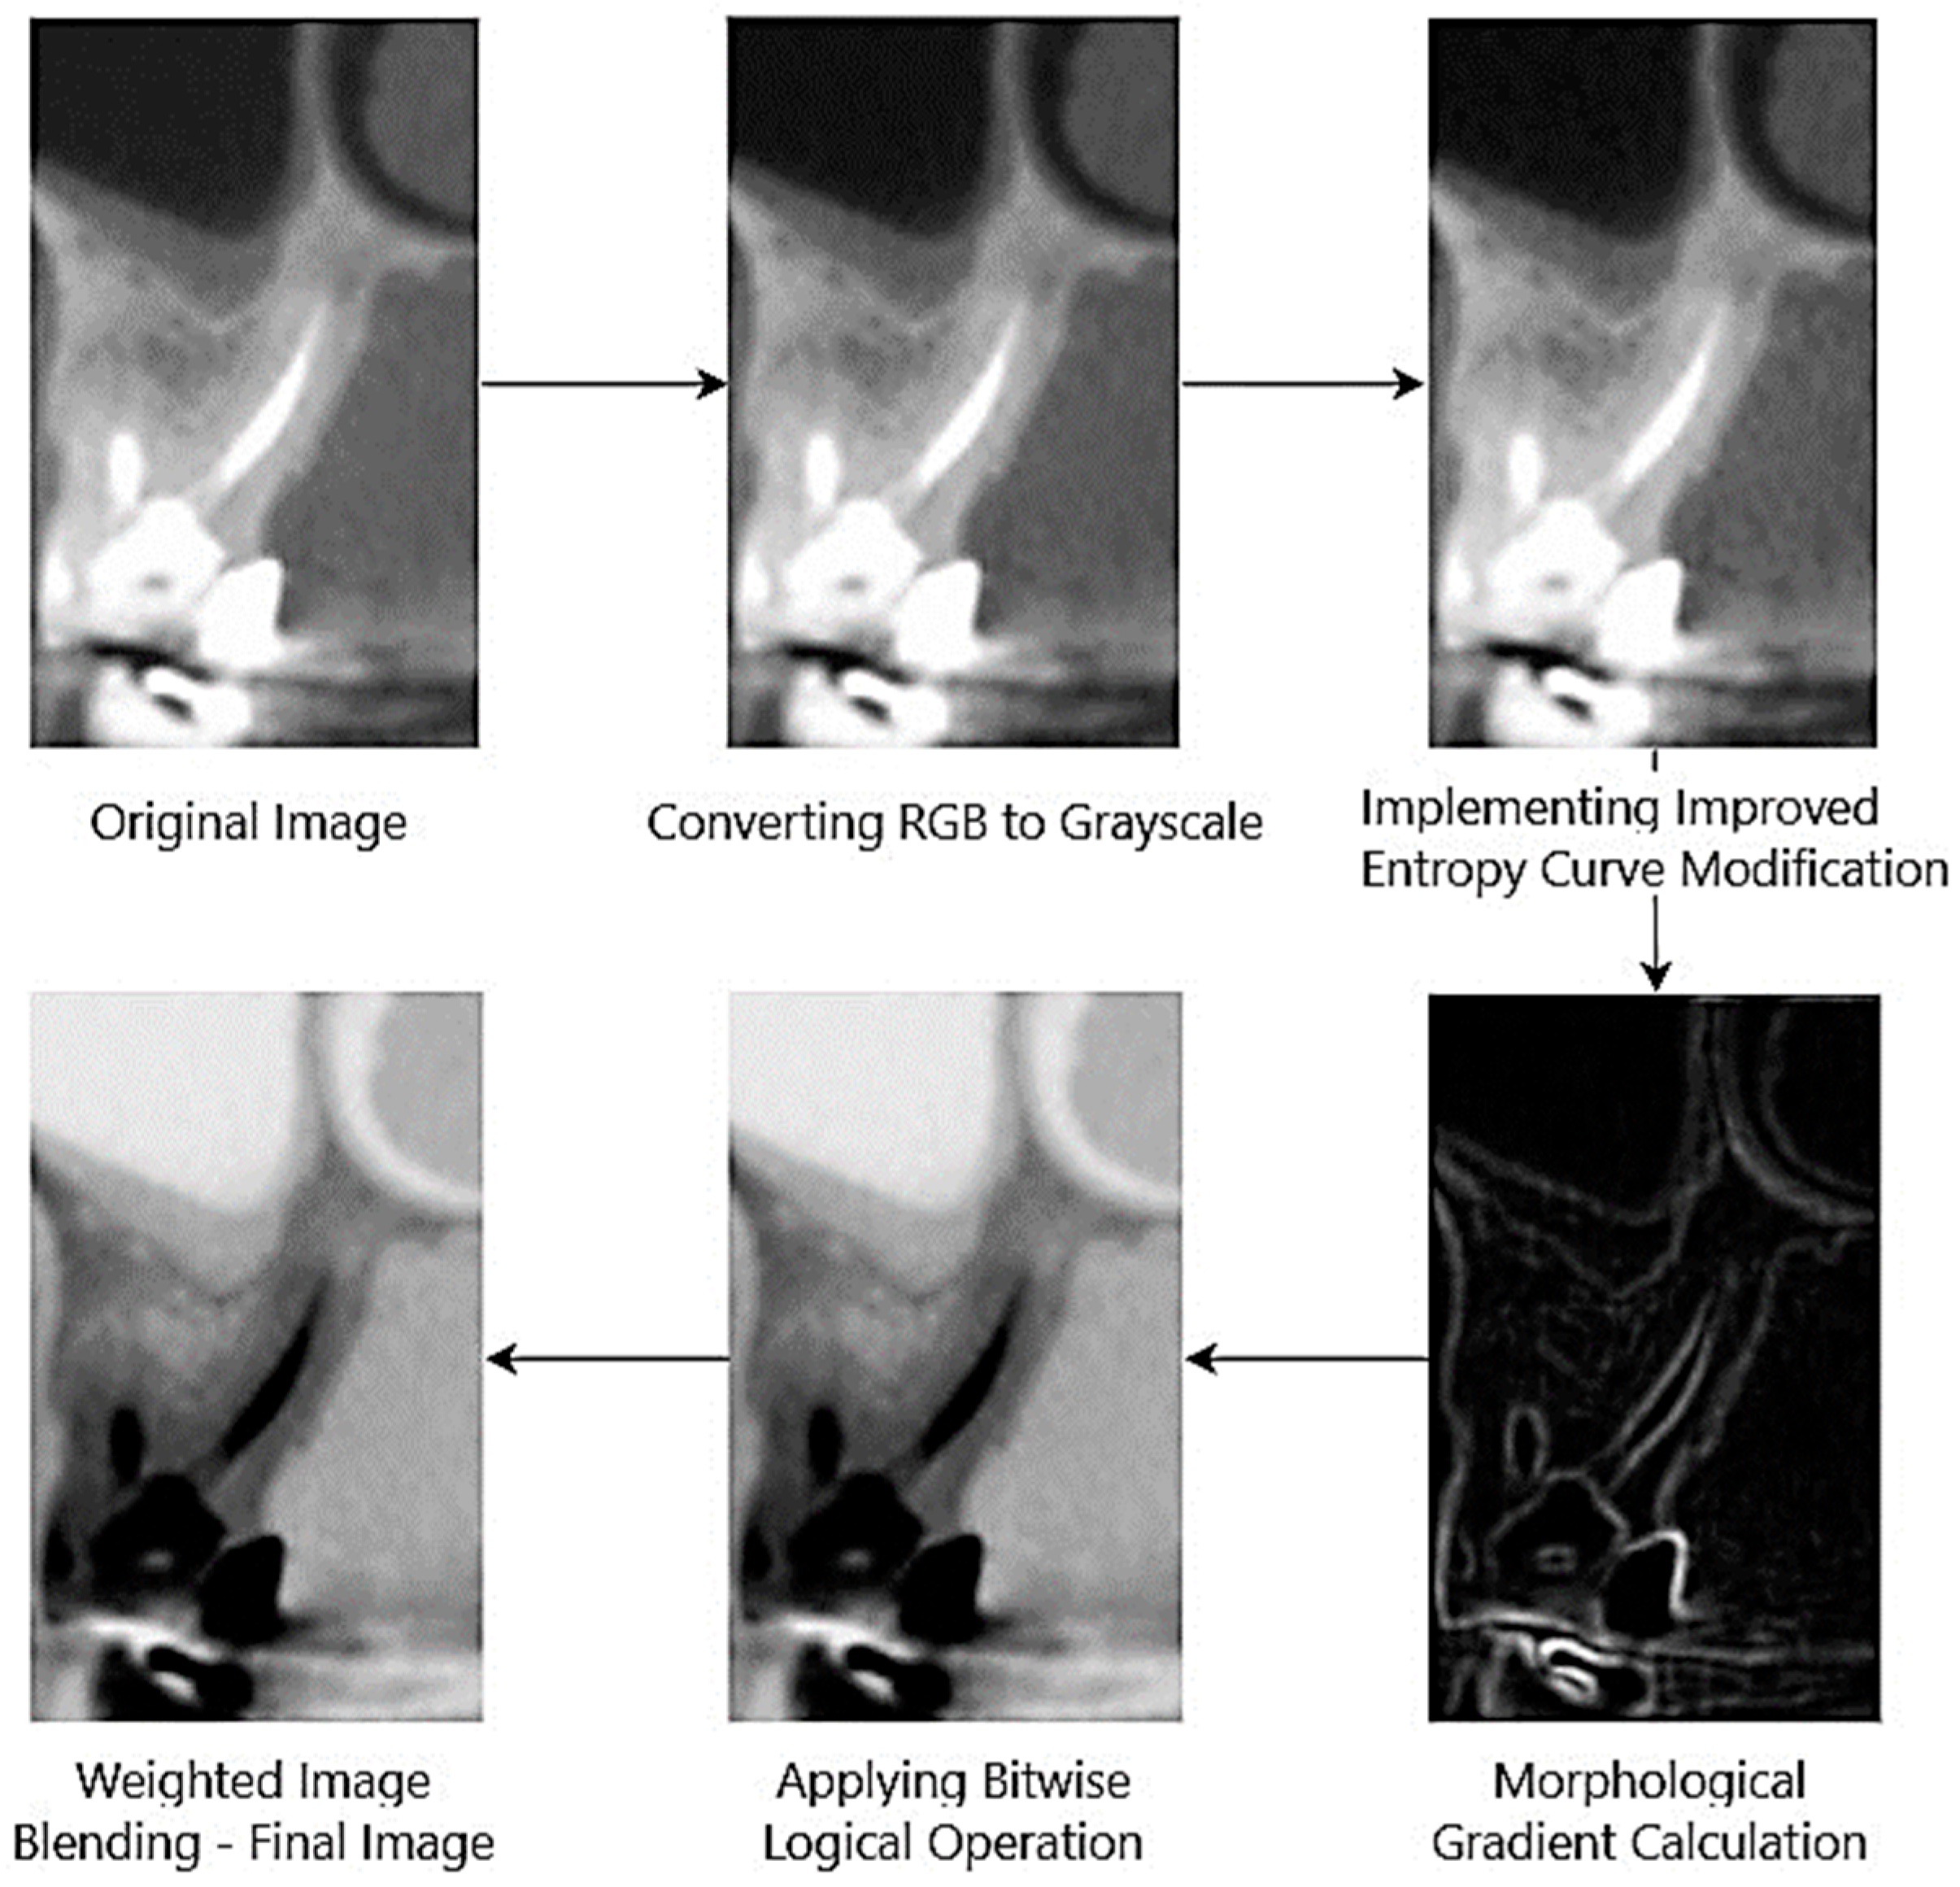

Datasets represent an important tool used in various analysis and research processes. They play a role in the evaluation of different classification and modeling methods. In this study, the UFPE dataset was used to classify tooth sections with and without lesions. The UFPE dataset was prepared for use in health research in Brazil and approved by the Local Research Ethics Committee of the University of Pernambuco. The dataset is divided into two main categories, healthy and unhealthy tooth samples, and contains a total of 1000 CBCT tooth scans. Each sample in this dataset is organized as pairs of images in both the coronal and sagittal planes [29]. Examples of lesioned and non-lesioned tooth sections in the dataset are presented visually in Figure 1.

The images labeled a and b in Figure 1 show slices representing tooth samples with and without lesions, respectively. The images used in the study were processed and analyzed in 186 × 115 dimensions, both in their original and enhanced versions. These images represent the different examples used to classify the tooth lesions in the dataset. The dataset has three different categories. These are no lesions, large lesions, and small lesions. The dataset is divided into two groups as 80% training data and 20% test data to test the accuracy of the model.

Figure 1. Examples of images with and without lesions in the UFPE dataset [30].